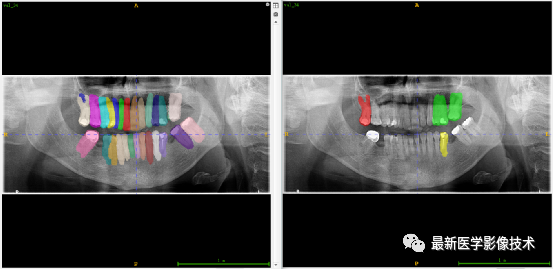

验证集牙齿分割计数和异常牙齿分割识别

左图是分割计数,右图是异常牙齿分割识别结果